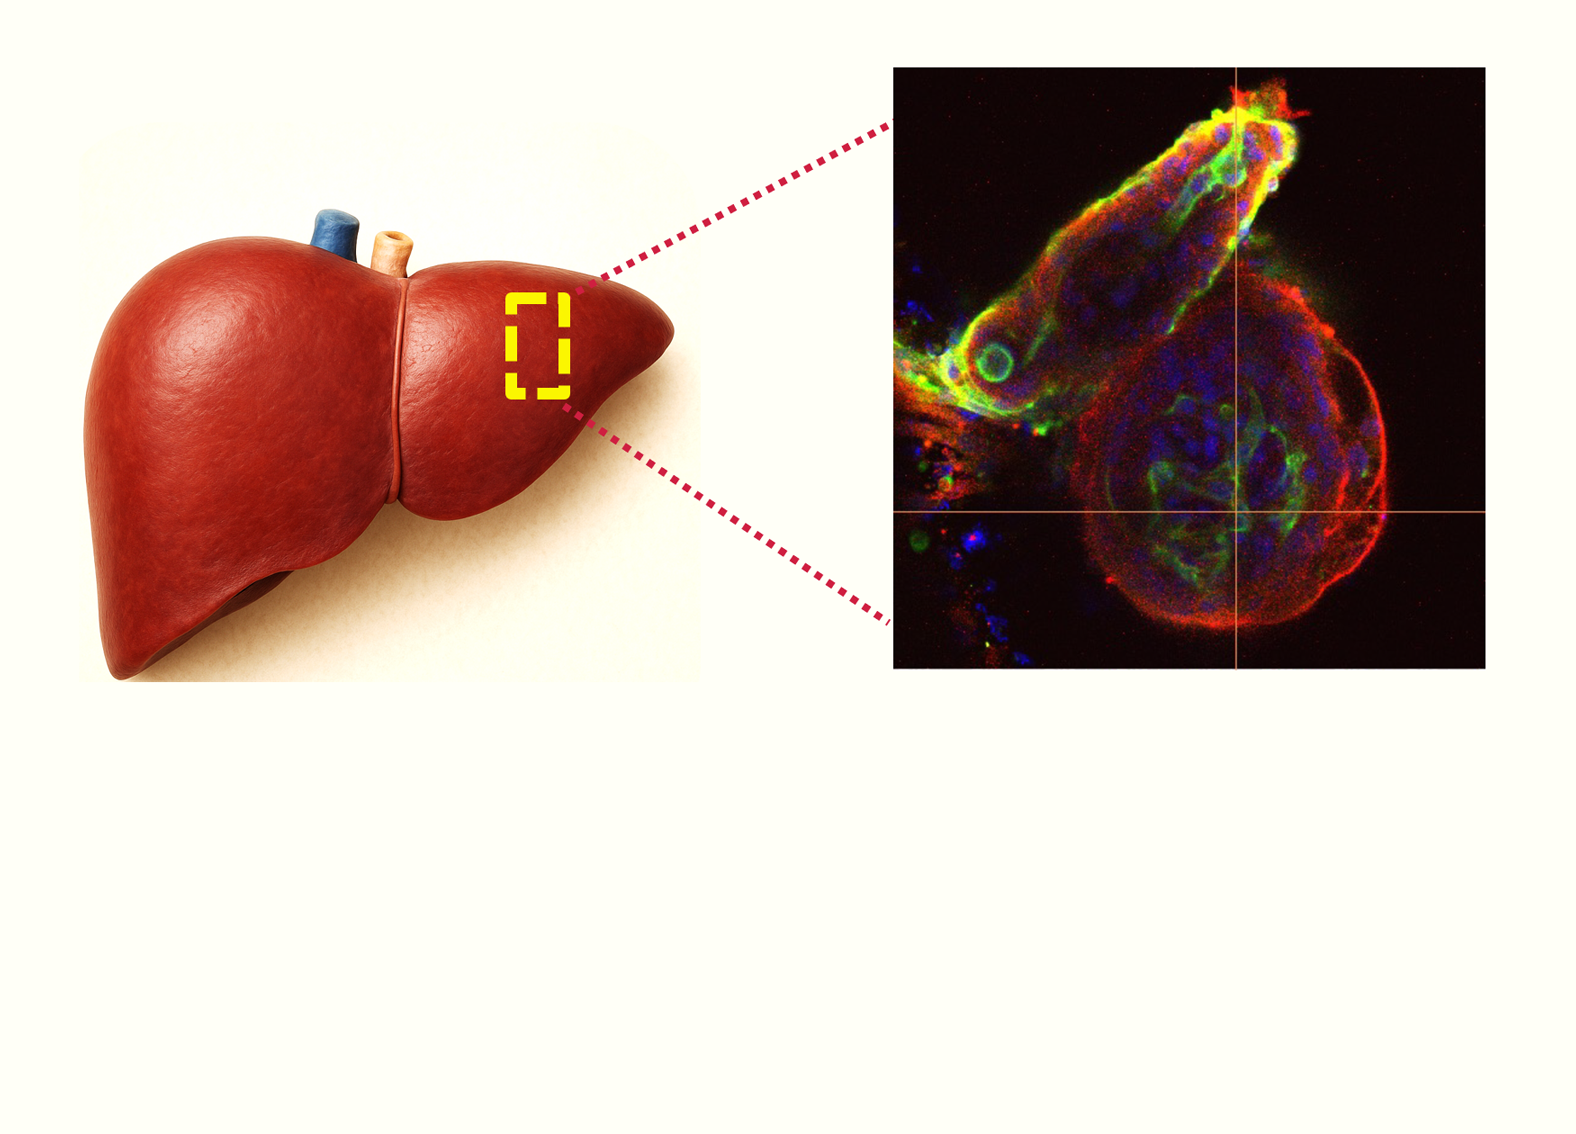

We create high-fidelity human tissues by integrating 3D bioprinting, organ-on-chip microfluidics, advanced biomaterials, AI-driven analytics and modeling. This enables us to predict drug safety and efficacy with unmatched accuracy, reducing time, cost, and reliance on animal testing.

High-fidelity human liver, heart, and other organs for predictive drug screening.

We deliver next-generation drug discovery services that replace outdated animal models with scalable, ethical, and predictive human tissue platforms. We integrate 3D bioprinting, organ-on-chip systems, AI analytics, and quantum modeling to help pharma de-risk pipelines and accelerate approvals.

Miniaturized human liver, heart, and other organ models for high-throughput screening.

Reduce the 90% failure rate of animal models with tissue platforms that mimic real human biology.